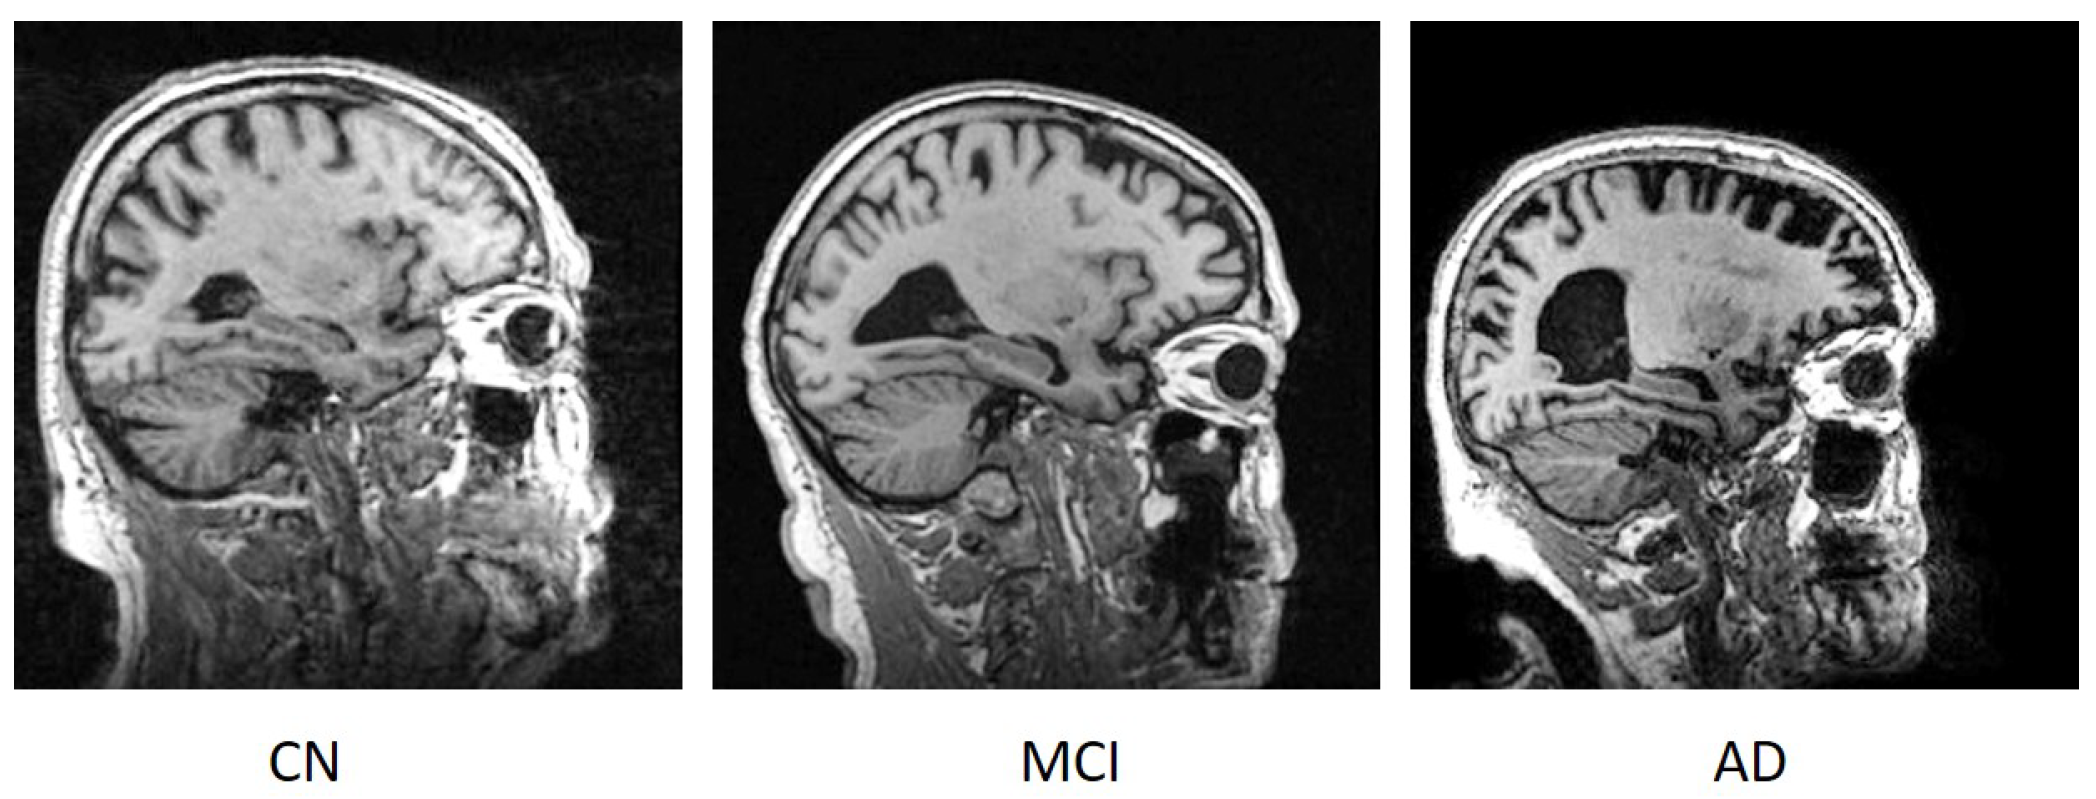

- Hazarika, R.A.; Maji, A.K.; Kandar, D.; Chakrabarti, P.; Chakrabarti, T.; Rao, K.J.; Carvalho, J.; Kateb, B.; Nami, M. An evaluation on changes in Hippocampus size for Cognitively Normal (CN), Mild Cognitive Impairment (MCI), and Alzheimer’s disease (AD) patients using Fuzzy Membership Function. OSF Preprints 2021. [Google Scholar] [CrossRef]

- Hazarika, R.A.; Maji, A.K.; Sur, S.N.; Olariu, I.; Kandar, D. A Fuzzy Membership based Comparison of the Grey Matter (GM) in Cognitively Normal (CN), Mild Cognitive Impairment (MCI), and Alzheimer’s Disease (AD) Using Brain Images. J. Intell. Fuzzy Syst. 2022; in press. [Google Scholar] [CrossRef]